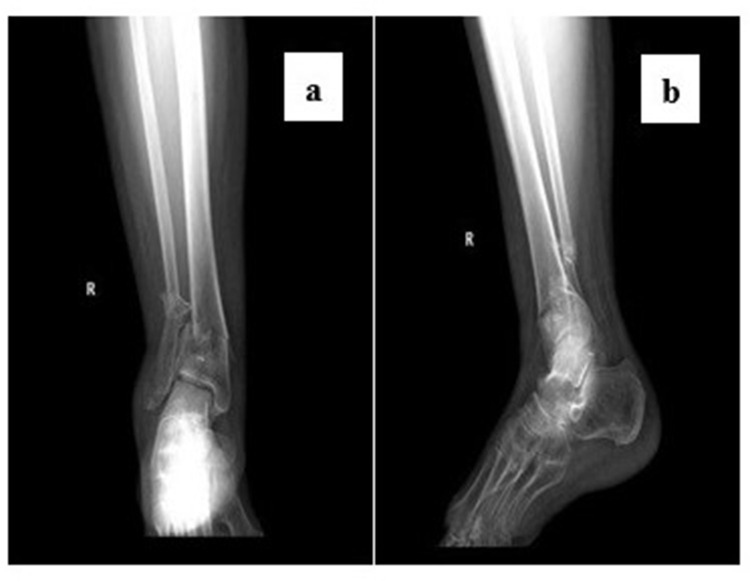

Patients and methods: In this single-center retrospective study, we collected adult (≥18 years old) patients with pilon fractures who underwent open reduction and internal fixation at Xi'an Honghui Hospital from January 2020 to July 2024 and had the cognitive ability to complete the questionnaire. Exclusion criteria included incomplete medical records, concurrent other foot fractures, or severe mental disorders. The preoperative central sensitization (CS) determination criteria were a score of ≥18 on the Chinese version of the 9-item Central Sensitization Inventory (CSI-9). The assessment indicators at baseline and the last follow-up included the Visual Analogue Scale (VAS) for pain, the American Orthopaedic Foot & Ankle Society Hindfoot Score (AOFAS), and the Hospital Anxiety and Depression Scale (HADS). Patients were divided into the CS group and the non-CS group based on whether they had a preoperative central sensitization state, and the differences in baseline characteristics, pain severity, functional performance, and psychological state between the two groups were compared.